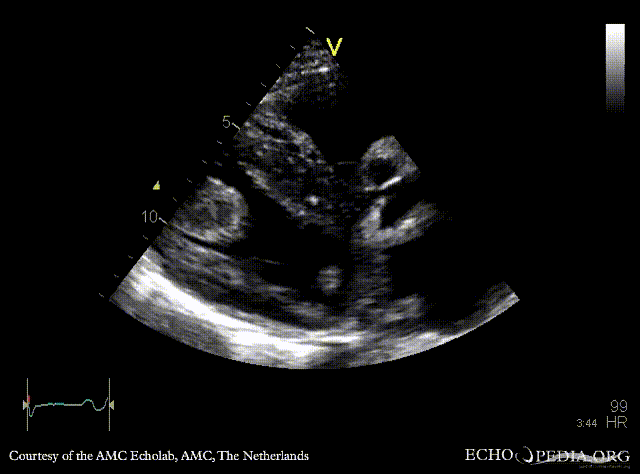

Case 142